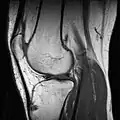

RM de um joelho.